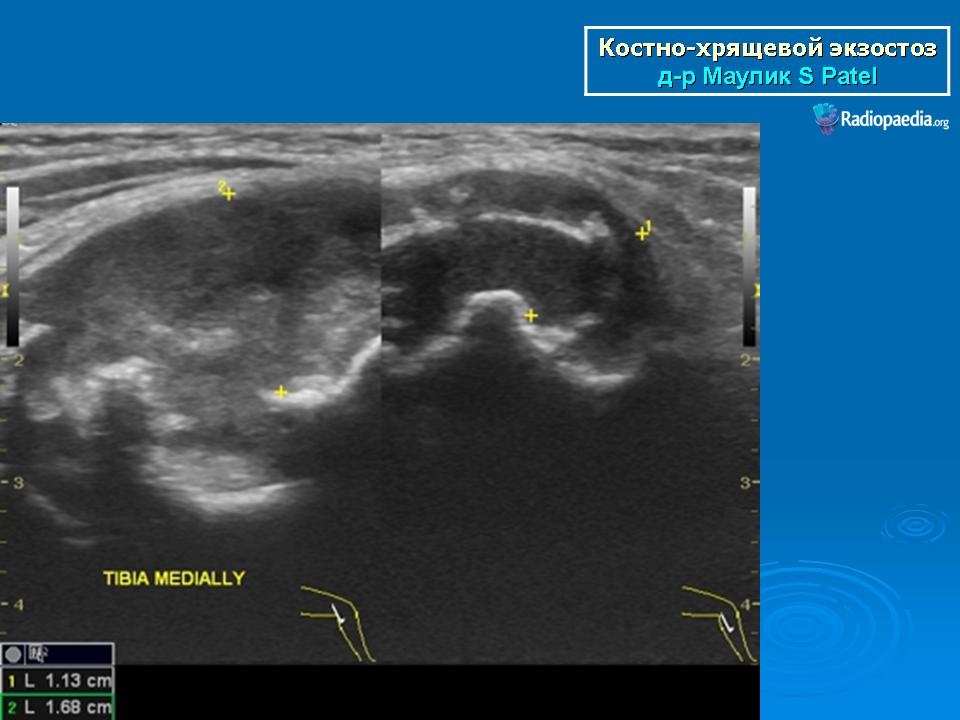

Костно-хрящевые экзостозы (остеохондрома).

Локализация остеохондромы: частота поражения отдельных костей различна; нижний коней бедренной кости, верхние отделы плечевой и большеберцовой костей поражаются более чем у половины больных. На всем протяжении остеохондрома покрыта надкостницей. Она может быть обнаружена и в других костях, за исключением костей лицевого черепа. Все же поражение костей позвоночника, кистей рук и стоп встречается редко. При рентгенологическом исследовании видна типичная картина узкого или широкого выроста вблизи эпифизарной части пораженной кости. Обычно плотность узла неоднородная, имеются многочисленные плотные участки, соответствующие обызвествленным хрящевым долькам. Хрящевая «шапочка» большей частью не определяется, поскольку хрящ остается необызвествленным. Она может быть выявлена только при магнитно-резонансной томографии.